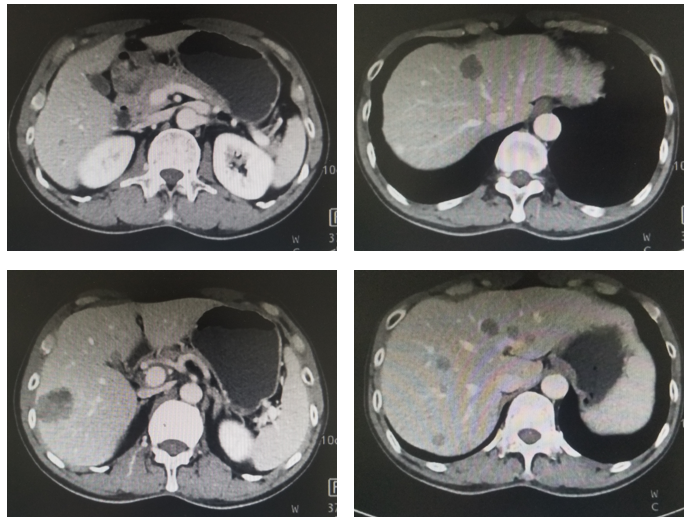

图4. 腹部CT平扫+强化(治疗后5月,2020年3月)

治疗:现给与卡培他滨+曲妥珠单抗+PD-1单抗维持治疗3周期,末次复查CT见图4,血肿瘤标志物AFP水平变化(图5)。

图5. 腹部CT平扫+强化(治疗后7月,2020年5月)

影像科:根据患者治疗前、治疗后首次及再次复查CT看,原发病灶胃壁增厚明显减轻,肝转移病灶明显缩小,部分病灶消失,首次CT判效PR,再次复查CT确认PR。提示内科治疗有效。

该患者为中年男性,首诊考虑AFP和HER-2双阳性的晚期胃癌合并多发肝转移,无根治性手术及转化治疗机会,晚期一线给与XELOX+曲妥珠单抗+PD-1单抗治疗7周期,期间复查CT确认PR,提示治疗有效,因奥沙利铂不良反应改为卡培他滨联合PD-1单抗维持治疗,治疗过程中肿瘤持续缩小,起病时异常增高的血肿瘤标志物AFP明显下降,目前继续维持治疗中。